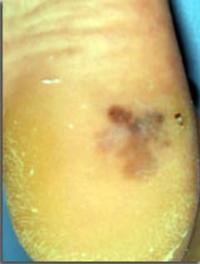

Lorsque le diagnostic de mélanome malin cutané est confirmé par l’examen histologique d’une lésion pigmentée enlevée chirurgicalement, [...]

Le mélanome cutané n’est pas le plus fréquent des cancers dermatologiques mais c’est assurément le plus mortel. Pour les patients diagnostiqués [...]

Alors qu’aux stades précoces, le mélanome malin peut être guéri par l’exérèse chirurgicale, le pronostic est beaucoup plus péjoratif [...]